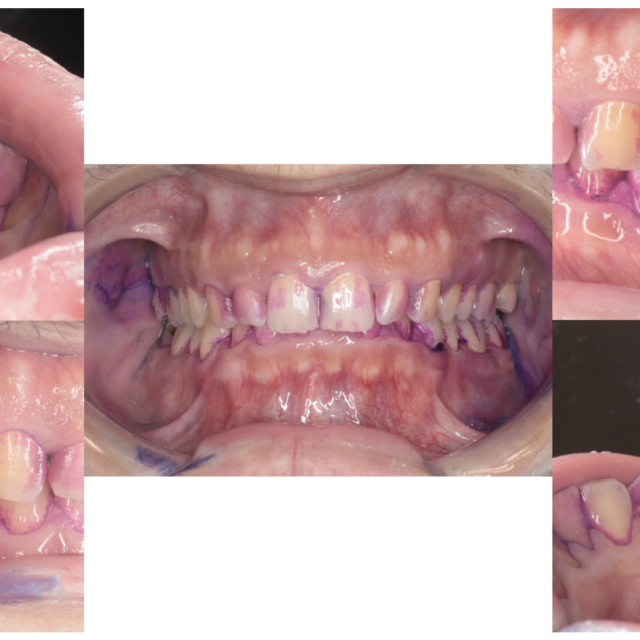

歯周病